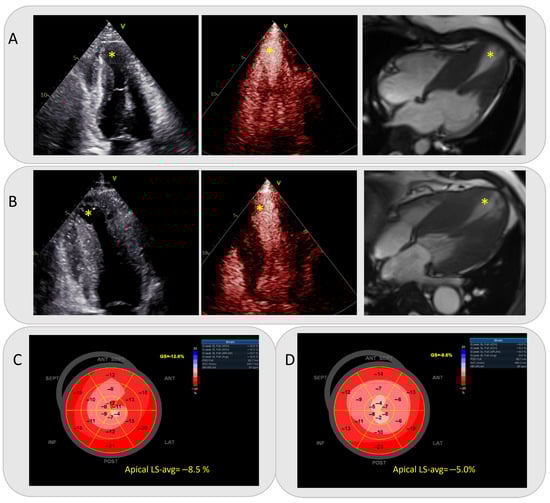

Incremental Value of Apical Longitudinal Strain in Predicting High-Risk Apical Aneurysms in Patients with Hypertrophic Cardiomyopathy

by Xin Hu, Xueqing Cheng, Yuwei Bao, Jie Tian, Shiliang Liu, Yaqin Yang, Qi Xu, Bingyi Zhang, Youbin Deng, Yongping Lu and Yani Liu

Diagnostics 2026, 16(4), 575; https://doi.org/10.3390/diagnostics16040575 (registering DOI) - 14 Feb 2026

Abstract

Background: Apical aneurysms have long been considered a critical risk marker for poor clinical outcomes in hypertrophic cardiomyopathy (HCM) individuals. This study aims to identify apical features associated with adverse outcomes and explore their incremental predictive value beyond the traditional sudden cardiac [...] Read more.

Background: Apical aneurysms have long been considered a critical risk marker for poor clinical outcomes in hypertrophic cardiomyopathy (HCM) individuals. This study aims to identify apical features associated with adverse outcomes and explore their incremental predictive value beyond the traditional sudden cardiac death (SCD) risk score model. Methods: From December 2019 to November 2024, 2318 HCM patients were diagnosed at Tongji Hospital. Ultimately, 65 HCM patients with apical aneurysms were included in the analysis, each having undergone conventional and contrast echocardiography, as well as speckle tracking echocardiography (STE). Results: With a median follow-up of 26 months, composite events occurred in 25 (38%) patients, while none occurred in 40 (62%). Multivariate Cox regression revealed that abnormal apical longitudinal strain average (LS-avg) significantly increased composite event risk (HR: 1.23; 95% CI: 1.02–1.48). For patients with a 5-year SCD risk score < 4% or aneurysm diameter < 20 mm, survival differed significantly between apical LS-avg ≥ −6.6% and <−6.6% (p < 0.05). Correct reclassification was 10.8% (7/65) for reduced 5-year SCD risk scores and 15.4% (10/65) for smaller aneurysms. Incorporating apical LS-avg into 5-year SCD risk score or aneurysm diameter assessment improved risk assessment (NRI: 67.7% and 66.2% for adverse event prediction). A likelihood ratio test showed that apical LS-avg enhanced prognostic accuracy in patients, with lower 5-year SCD risk scores and smaller aneurysms (all p < 0.001). Conclusions: Apical LS-avg may be associated with an increased risk of adverse cardiovascular events in HCM individuals who had apical aneurysms. On the basis of the conventional 5-year SCD risk score and aneurysm size, apical LS-avg may have the potential to be used to individually identify the high-risk group of this patient cohort, particularly among those with a 5-year SCD risk score < 4% and an aneurysm diameter < 20 mm. Full article

(This article belongs to the Section Clinical Diagnosis and Prognosis)

Show Figures

Figure 1